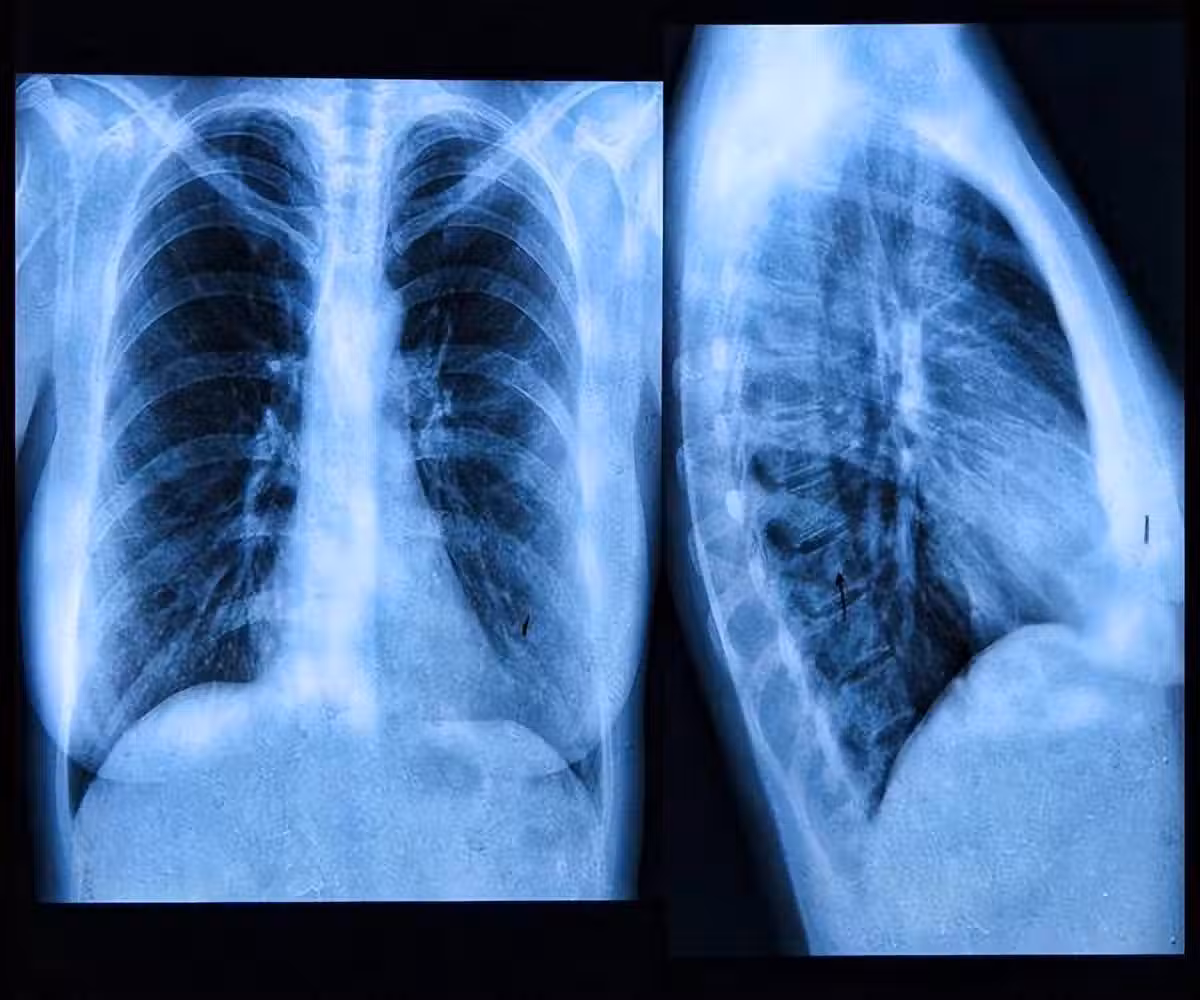

肺內有癌,腿疼告知?事實上,早期肺癌的5個跡象你更需要去關注!

4、肺部持續疼痛

如果人的肺部持續疼痛,也有可能是肺癌造成的,隨著病情的發展,肺癌也會引起骨骼疼痛和肌肉疼痛。

這種痛感多發生在背部和肩部,運動程度越大,疼痛感也會有所增加。因此患上肺癌是禁止做任何劇烈運動的。